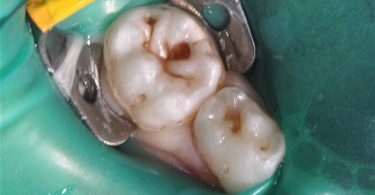

Foi realizado um exame clínico e radiológico inicial (fig. 1 a 3), tendo sido diagnosticada, entre outras lesões de cárie, uma lesão de cárie profunda com atingimento pulpar no segundo molar temporário inferior direito (fig. 3). Foi proposta a realização de uma pulpotomia com agregado trióxido mineral (MTA) e a colocação de uma coroa pré-formada. As várias possibilidades restauradoras foram apresentadas e discutidas com os pais, que decidiram optar pela colocação de uma coroa pré-formada de zircónia, por motivos estéticos.

Foi também sugerida a realização de sedação consciente devido à história prévia de falta de colaboração do paciente, tendo sido também aceite pelos responsáveis o recurso a esta técnica de controlo de comportamento, o que possibilitou a execução do plano de tratamento estipulado (fig. 4).

Após a anestesia e a colocação do isolamento absoluto com dique de borracha (fig. 5) foi iniciado o preparo dentário para a colocação de uma coroa de zircónia pré-formada, seguindo as instruções do fabricante. Inicialmente, foi realizada uma redução da superfície oclusal de 1-2 mm, seguindo o contorno oclusal, com uma broca em chama de vela diamantada (fig. 6). De seguida, foi efetuada uma redução supragengival de todas as paredes dentárias com uma inclinação ligeiramente convergente para oclusal. Foram eliminados os contactos interproximais e toda a coroa clínica foi reduzida em cerca de 20-30%, seguido de um cuidadoso desgaste com uma broca em fio de faca diamantada da margem da preparação, cerca de 1-2 mm infragengival, para eliminar todas as margens ou degraus. Todas as linhas de ângulo foram ligeiramente arredondadas (fig. 7).